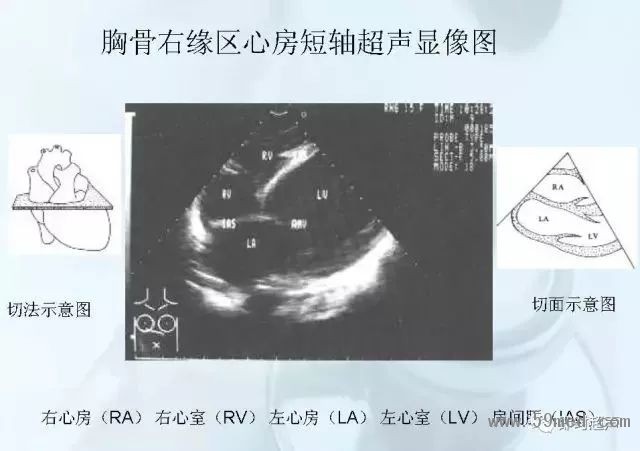

新聞中心 收藏!正常B超解剖圖譜,超實用!